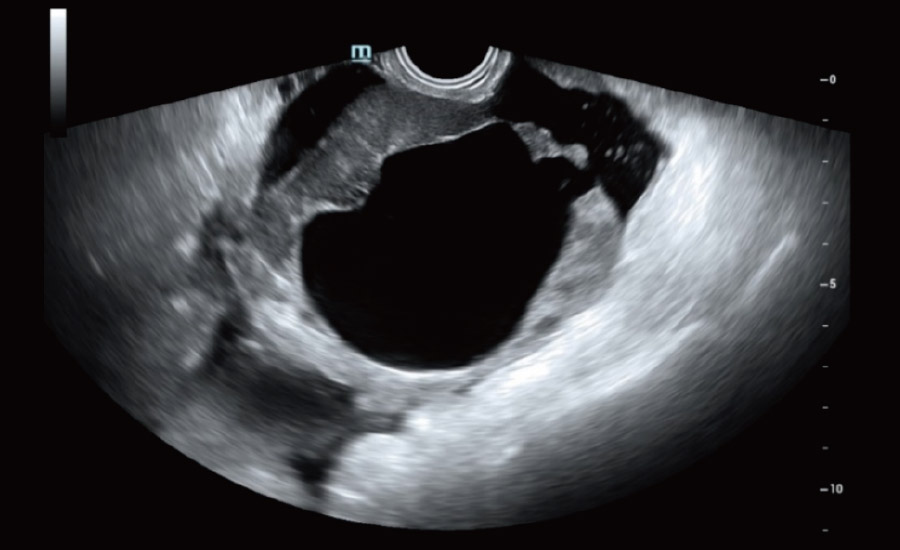

UMA (Ultra-Micro Angiography)

The innovative technology breaks the bottlenecks of traditional Doppler imaging. With ultra-high spatial resolution and flow sensitivity, it allows detecting super-subtle and super-slow flow perfusions, thereby extending the clinical application of qualitative and quantitative ultrasound evaluation in fetal brain, kidney, placenta, endometrium, ovary, etc.

UMA - uterine and endometrial flow